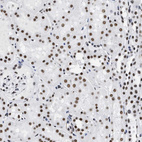

Immunohistochemical staining of human cerebral cortex, gastrointestinal, kidney and lymphoid tissues using Anti-LUC7L3 antibody HPA018484 (A) shows similar protein distribution across tissues to independent antibody HPA018475 (B).